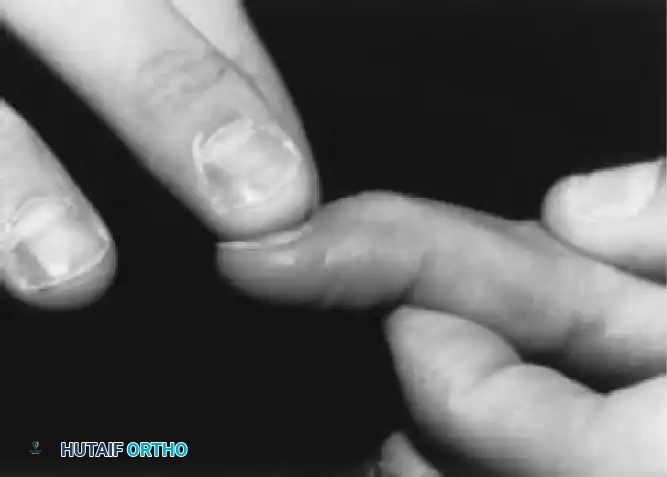

The Bunnell Test for Intrinsic Tightness:

To perform this test, the MCP joint is passively held in maximum extension. This maneuver places the intrinsic muscles on stretch. If the intrinsics are tight, passive flexion of the PIP joint is prevented or significantly limited. Conversely, when the MCP joint is passively flexed (relaxing the intrinsics), passive flexion of the PIP joint increases.

Fig. 70-11 The Bunnell test for intrinsic tightness. Extension of the MCP joint exacerbates PIP extension forces if the intrinsics are contracted.

Surgical Warning: With ulnar drift of the fingers, intrinsic tightness may be present only on the ulnar side. To test this accurately, axial alignment of the finger with the metacarpal must be maintained. Any ulnar deviation at the MCP joint during the test slackens the intrinsics on the ulnar side and will yield a false-negative result.